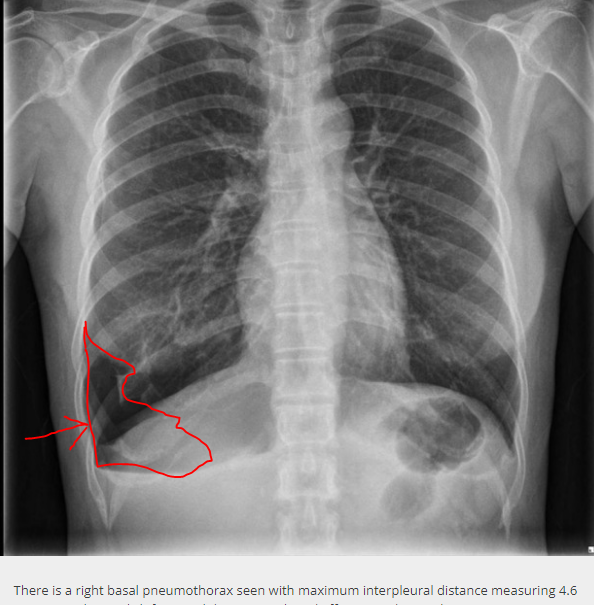

Natuurlijk kan de onderkant los gaan liggen als de bovenkant door de eerdere ingrepen wel vast blijft zitten. Voorbeeld zie je in de bijlage (gewoon van internet geplukt)